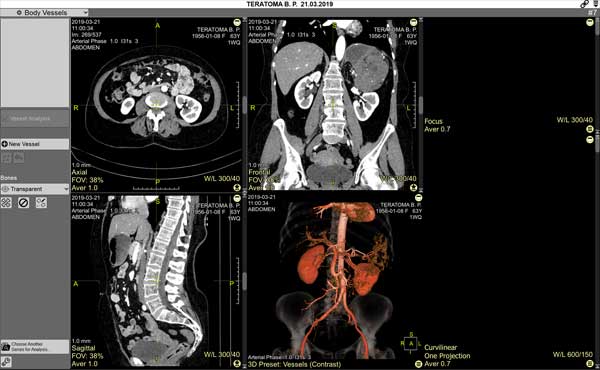

The screen will be split into 6 panels:

Four panels for vessel selection:

three standard orthogonal MPR projections

one - 3D model

Two panels with the tracing result: longitudinal view and cross-section

Images in them will appear after the vessel is constructed